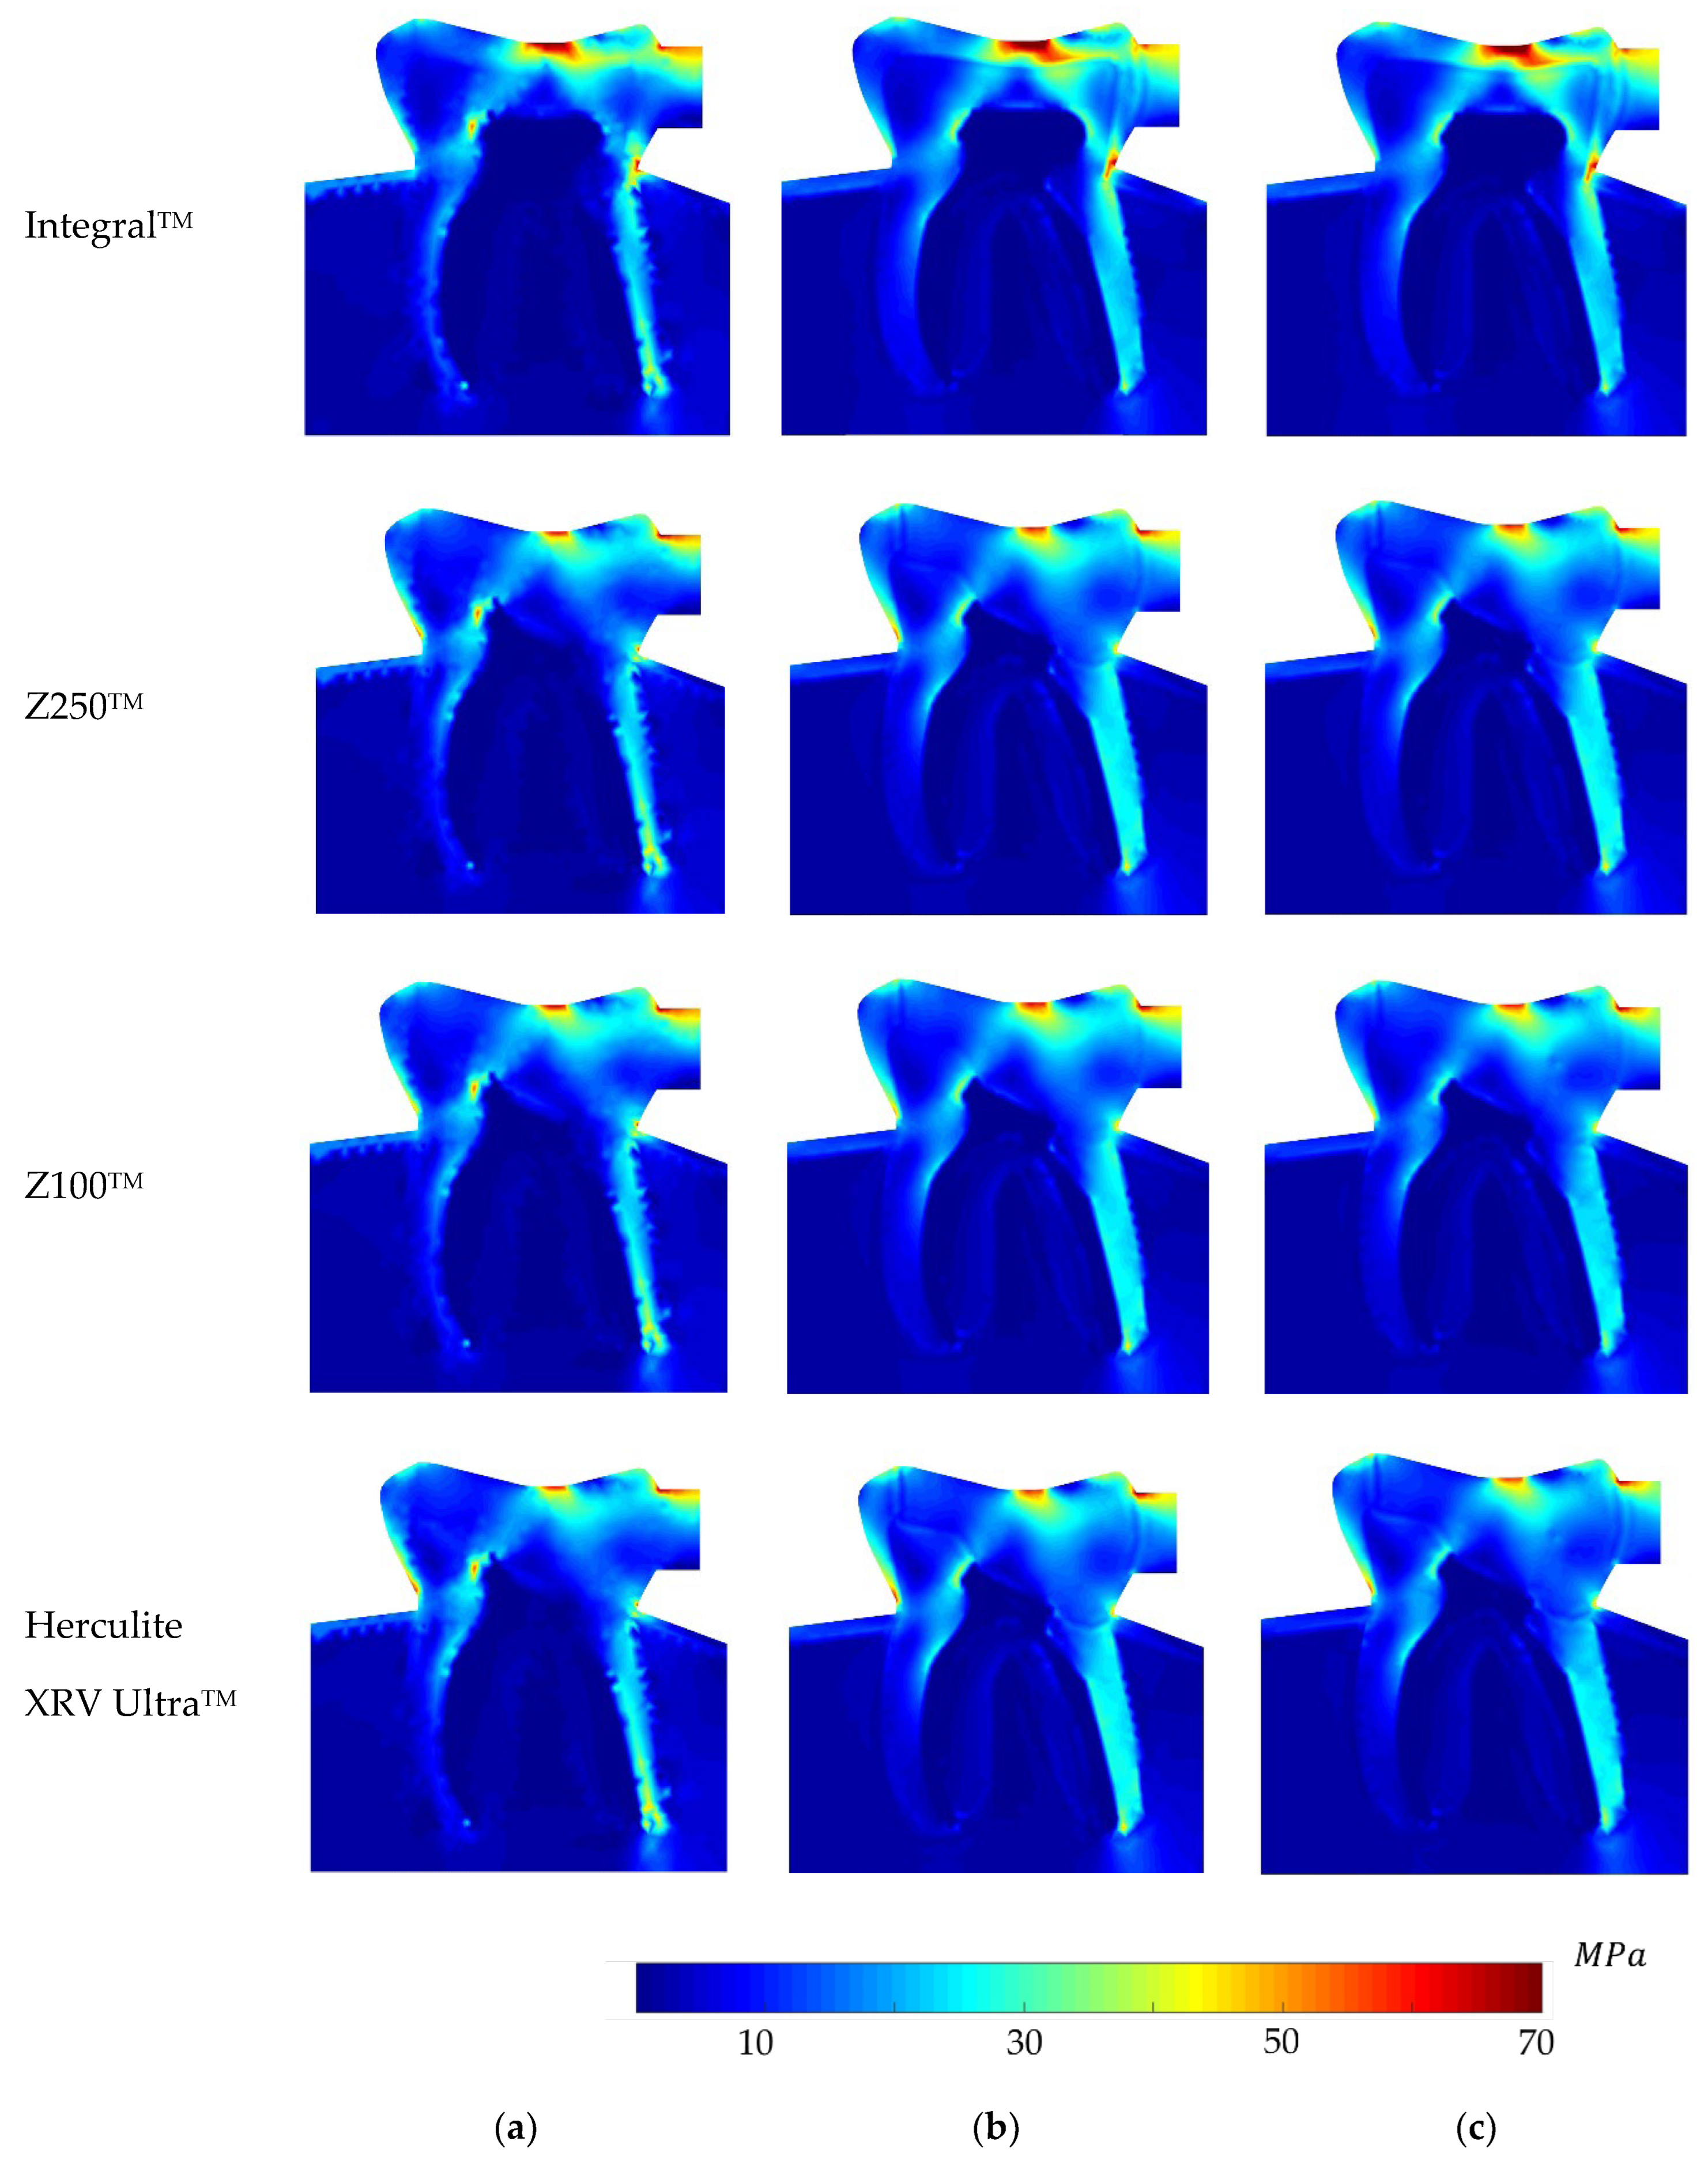

5. Analysis and Results

6. Discussion on the Results

- The non-restored tooth is characterised by enamel rather than composite restoration. Enamel exhibits the highest Young’s modulus compared to the composites. Consequently, an integral tooth demonstrates a greater ability to withstand forces compared to composite restorations. It means that the stiffness of enamel is higher than that of the restorative materials.

- The ranking on the local stress analysis can be rationalised based on the superior mechanical properties of Z100TM, including its elevated Young’s modulus, notably higher tensile and compressive strength compared to other composite materials. This implies that dental restoration using Z100TM results in increased stiffness and rigidity in the treated tooth. It owns the highest percentage of fillers, 66%, which implies higher hardness.

- Herculite XRV UltraTM exhibited the weakest response in terms of elasto-static analysis. One potential reason could be attributed to its lower Young’s modulus and consequently, the lowest hardness, which may be influenced by the presence of barium glass filler in this composite. Conversely, the Zirconia Filler in Z100TM and Filtek Z250TM might account for the improved physical properties observed in these two composites.

- In the depicted stress profiles of the BLV load case, where there is no tooth on the left side of the model (no essential boundary condition), the stress distribution shows higher value on critical regions, mostly close to the boundaries. The absence of essential boundary conditions on the left side of the 2D model in the BLV and OLV load cases leads the applied force to produce a higher level of stress on the borders and critical spots. In this regard, the global stress distribution maps obtained with the meshless methods clearly show the potential rupture lines. This study shows the importance of the neighbour tooth to prevent a potential fracture.